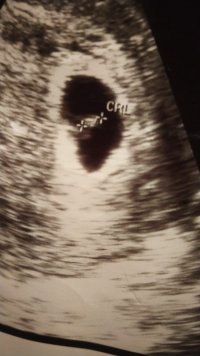

Selamlar hayatım. Resim inanılmaz derecede bulanık daha net resim var ise atın bakalım. Bu tür durumlarda tahmin inanılmaz şekilde zor oluylor. Yani söylemek için de söylemek bizlere uymuyor istiyoruz ki gördüğümüzü söyleyelim ama göremiyoruz 🙂

Bi tanem tekrar selamlar yok hayatım çok küçük vallahi göremiyorum hakkını helal et lütfen. Resimler olmuş sıkıntı yok ama sıkıntı görünmeyecek kadar yeni ve küçük olması netlik yok hayatım kusura bakma lütfen.

Yok estagfurullah ne demek allah razı olsun siz helal edin baktınız yinede minnettarım cok teşekkür ederim 6 haftalık burda oyuzden sanırım 2 hafta sonra kontrolüm var 8 haftalık olanı attıgımda onada bakıp yorumlarmısınız peki lütfenn